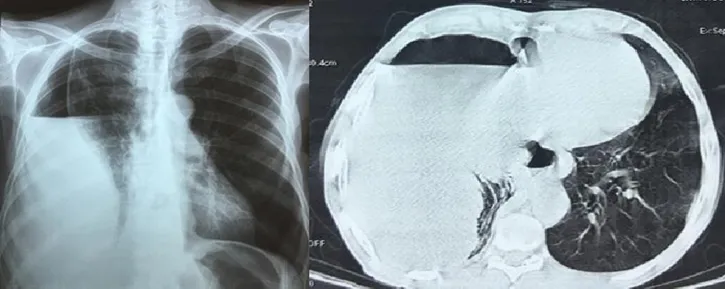

Results Observation 1Mr A.T. aged 18, without any particular pathological history, which had right basithoracic pain for 10 days, purulent bronchial syndrome, low abundance hemoptysis and effort dyspnea, without hydatidotysis evolving in a context of febrile sensations and conservation of the general condition. The clinical examination had found a right posterobasal fluid effusion syndrome. The chest X-ray had shown a right paracardiac hydro-aeric image of thoracoabdominal seat performing the classic iceberg image (Fig-1). At the thoracic-abdominal CT, a diaphragmatic cystic image was found, measuring 95/85 cm, with a hydro-aeric level within it (Fig-2). The assessment of the hydatid disease had not found any other intra- or extra-abdominal localizations.

Fig-1: Chest x-ray showing a right paracardiac hydro-aeric image «iceberg image»

Fig-2: Thoraco-abdominal scanner showing a diaphragmatic cystic image measuring 95/85 cm, with an hydro- aeric level and floating membranes